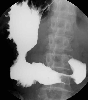

A case of gastric malignant lymphoma resembling type 3 advanced gastric cancer.

X-ray

Malignant Lymphoma/Malignant lymphoma

Untypical case